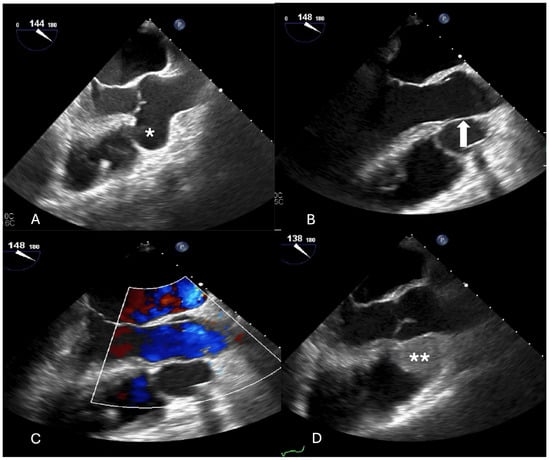

The repair consisted of a xeno-pericardial patch closure of the defect from inside the aortic root (Figure 1) while both commissures of the aortic valve between the non-coronary cusp and the left, respective right coronary cusp were resuspended with a transaortic stitch reinforced by a small xeno-pericardium pledget. Thereafter, the right atrium was opened and the defect was closed with a second patch on the atrial side.

Figure 1. (A) View on the aortic root with a large entrance in the sinus of valsalva aneurysm between the aortic sinus and the anterior leaflet of the mitral valve (white *). (B) A small piece of xeno-pericardium has been prepared to close the entrance of the non-coronary sinus aneurysm from the aortic root. (C) Intraoperative site following closure of the aneurysm on the aortic root side. (D) Intraoperative view following closure from the atrial side (through the right atrium, the forceps hold the tricuspid valve).